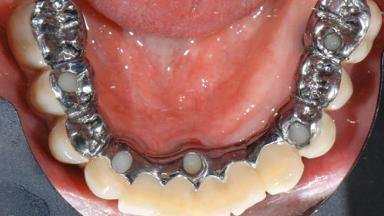

A 77-year-old male patient was referred for the management of frequent and repeated acrylic fracture of his existing mandibular fixed full-arch implant-supported metal/acrylic prosthesis. He also complained about softtissue soreness and the lack of retention and stability of his maxillary removable partial metal/acrylic prosthesis. Both prostheses had been delivered two years previously as part of his full-mouth rehabilitation (caries, tooth wear, tooth fracture). His medical history revealed high blood pressure, controlled with the use of antihypertensive medication.

Retention Screw-retained, with 4 or more splinted implants Screw-retained, with 4 or more splinted implants

Inter-Arch Distance Excessive (mechanical leverage issues) or restricted (space for components)

Bruxism Present